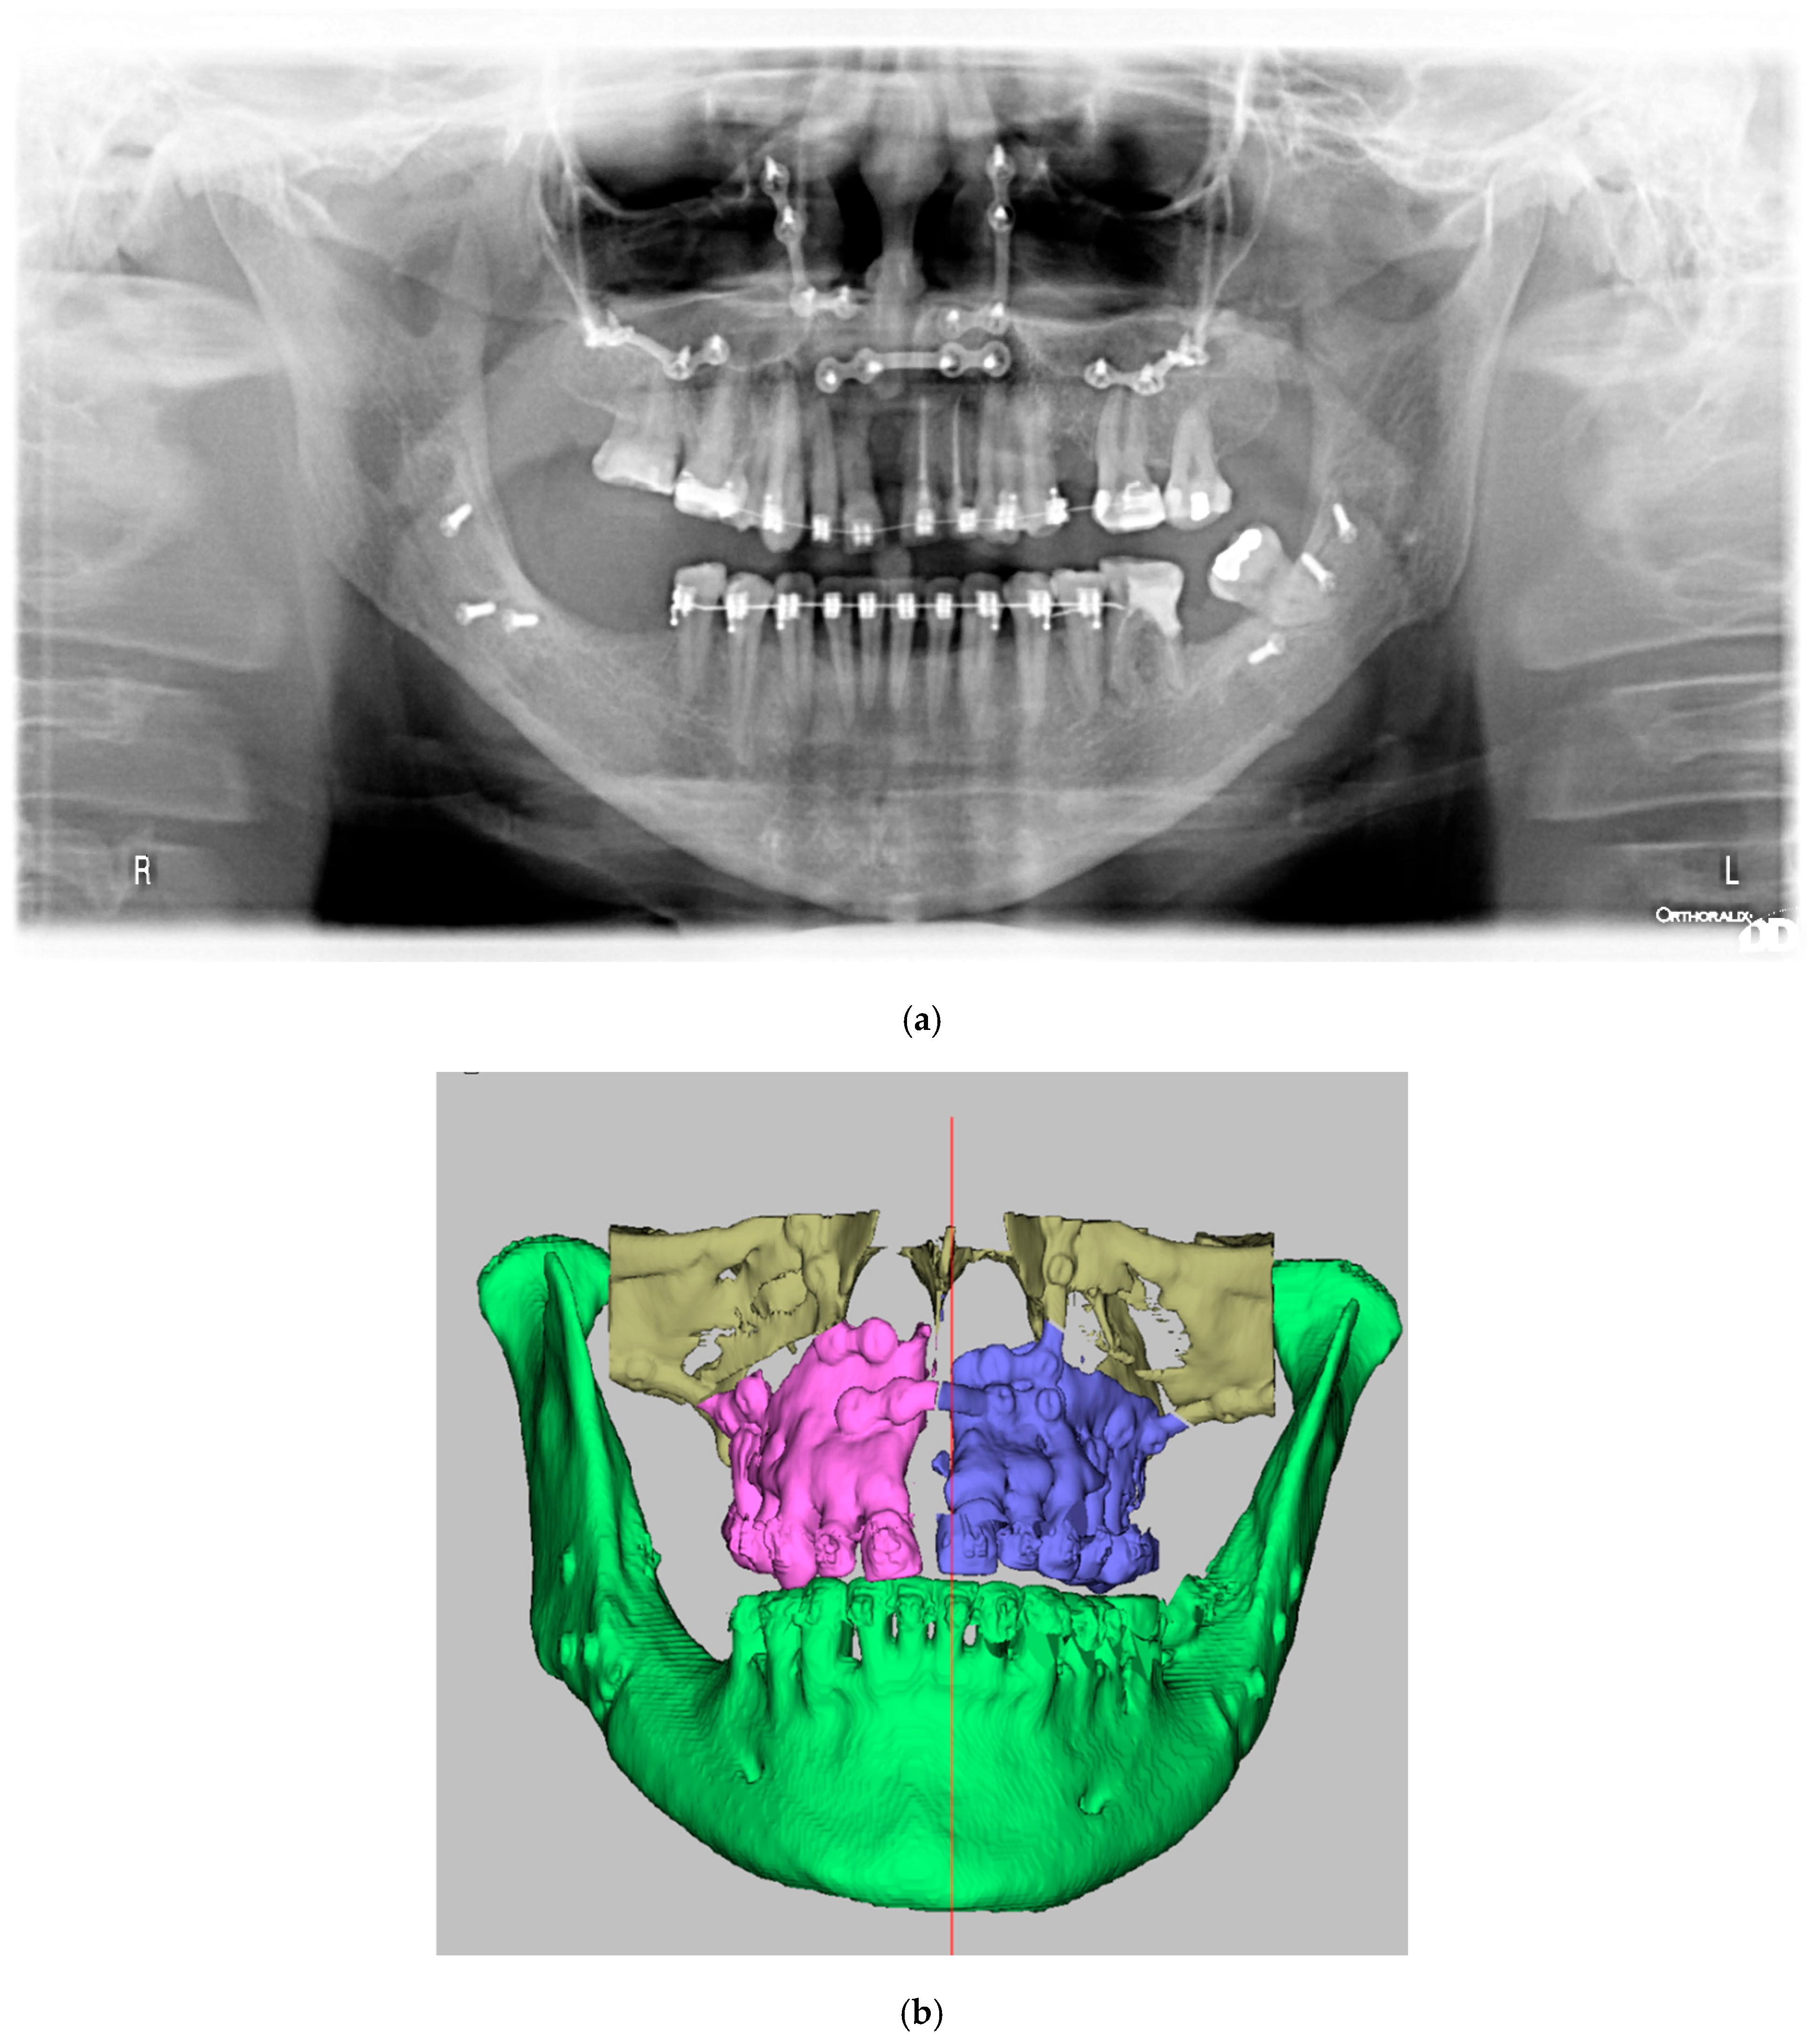

2.4. Surgical Phase

3. Discussion